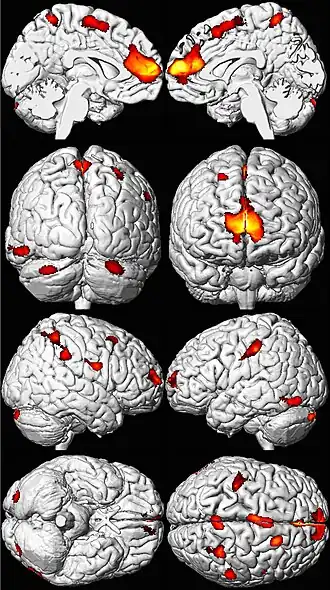

Effets à long terme sur le cerveau et la psyché

Les zones de perte de volume cérébral apparaissent ici en couleur sur un modèle de cerveau normal[201].

L'exposition de l'embryon ou de l'enfant, jusqu'à l'adolescence peut avoir des effets différés délétères et graves, parfois irréversibles, qui commencent à préoccuper le politique, les responsables de la santé, les assureurs et certains économistes.